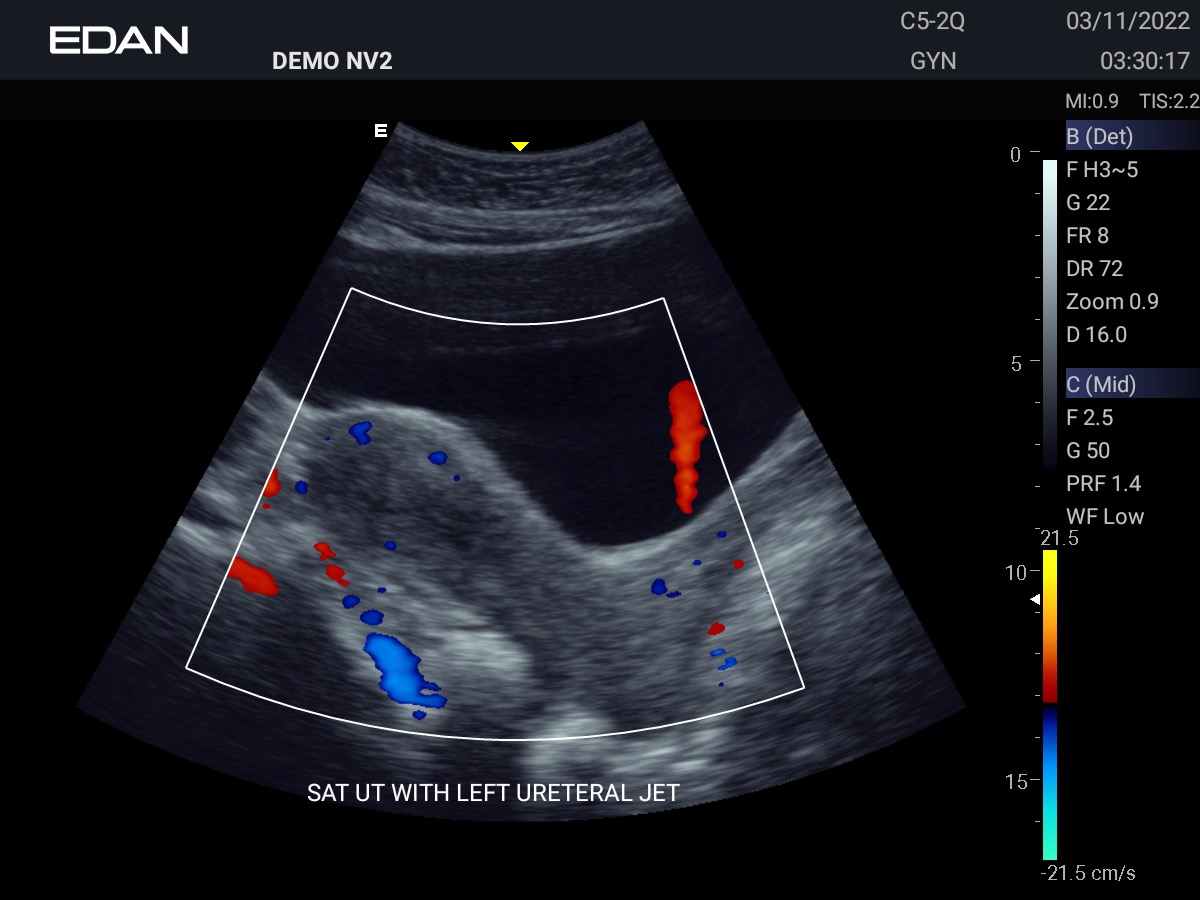

Clareza impressionante

Construído com a inovadora tecnologia Edan TAI e várias tecnologias de processamento de imagem, o Acclarix AX3 pode exibir perfeitamente a imagem de ultrassom em diferentes modos, auxiliando o ultrassonografista a fazer diagnósticos mais precisos.

- OB/GIN

Galeria de Imagens